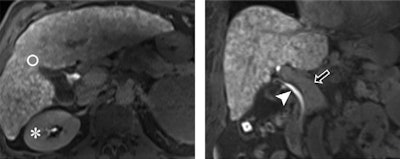

The FLIS combines the three following components:

- An enhancement quality score based on whether the liver is hypointense, isointense, or hyperintense, relative to the right kidney

- An excretion quality score, which indicates the degree of contrast agent excretion into the biliary tract

- A portal vein sign quality score based on whether the portal vein is hyperintensive, isointensive, or hypointense compared with the liver parenchyma

As the sum of all three parameters, which are equally influential in determining the condition of a patient with chronic liver disease and their chance for survival, the FLIS ranges from 0 to 6 points. For the current study, the researchers hypothesized that "patients with a low FLIS are at higher risk for the development of hepatic decompensation and mortality compared with patients with a high FLIS."